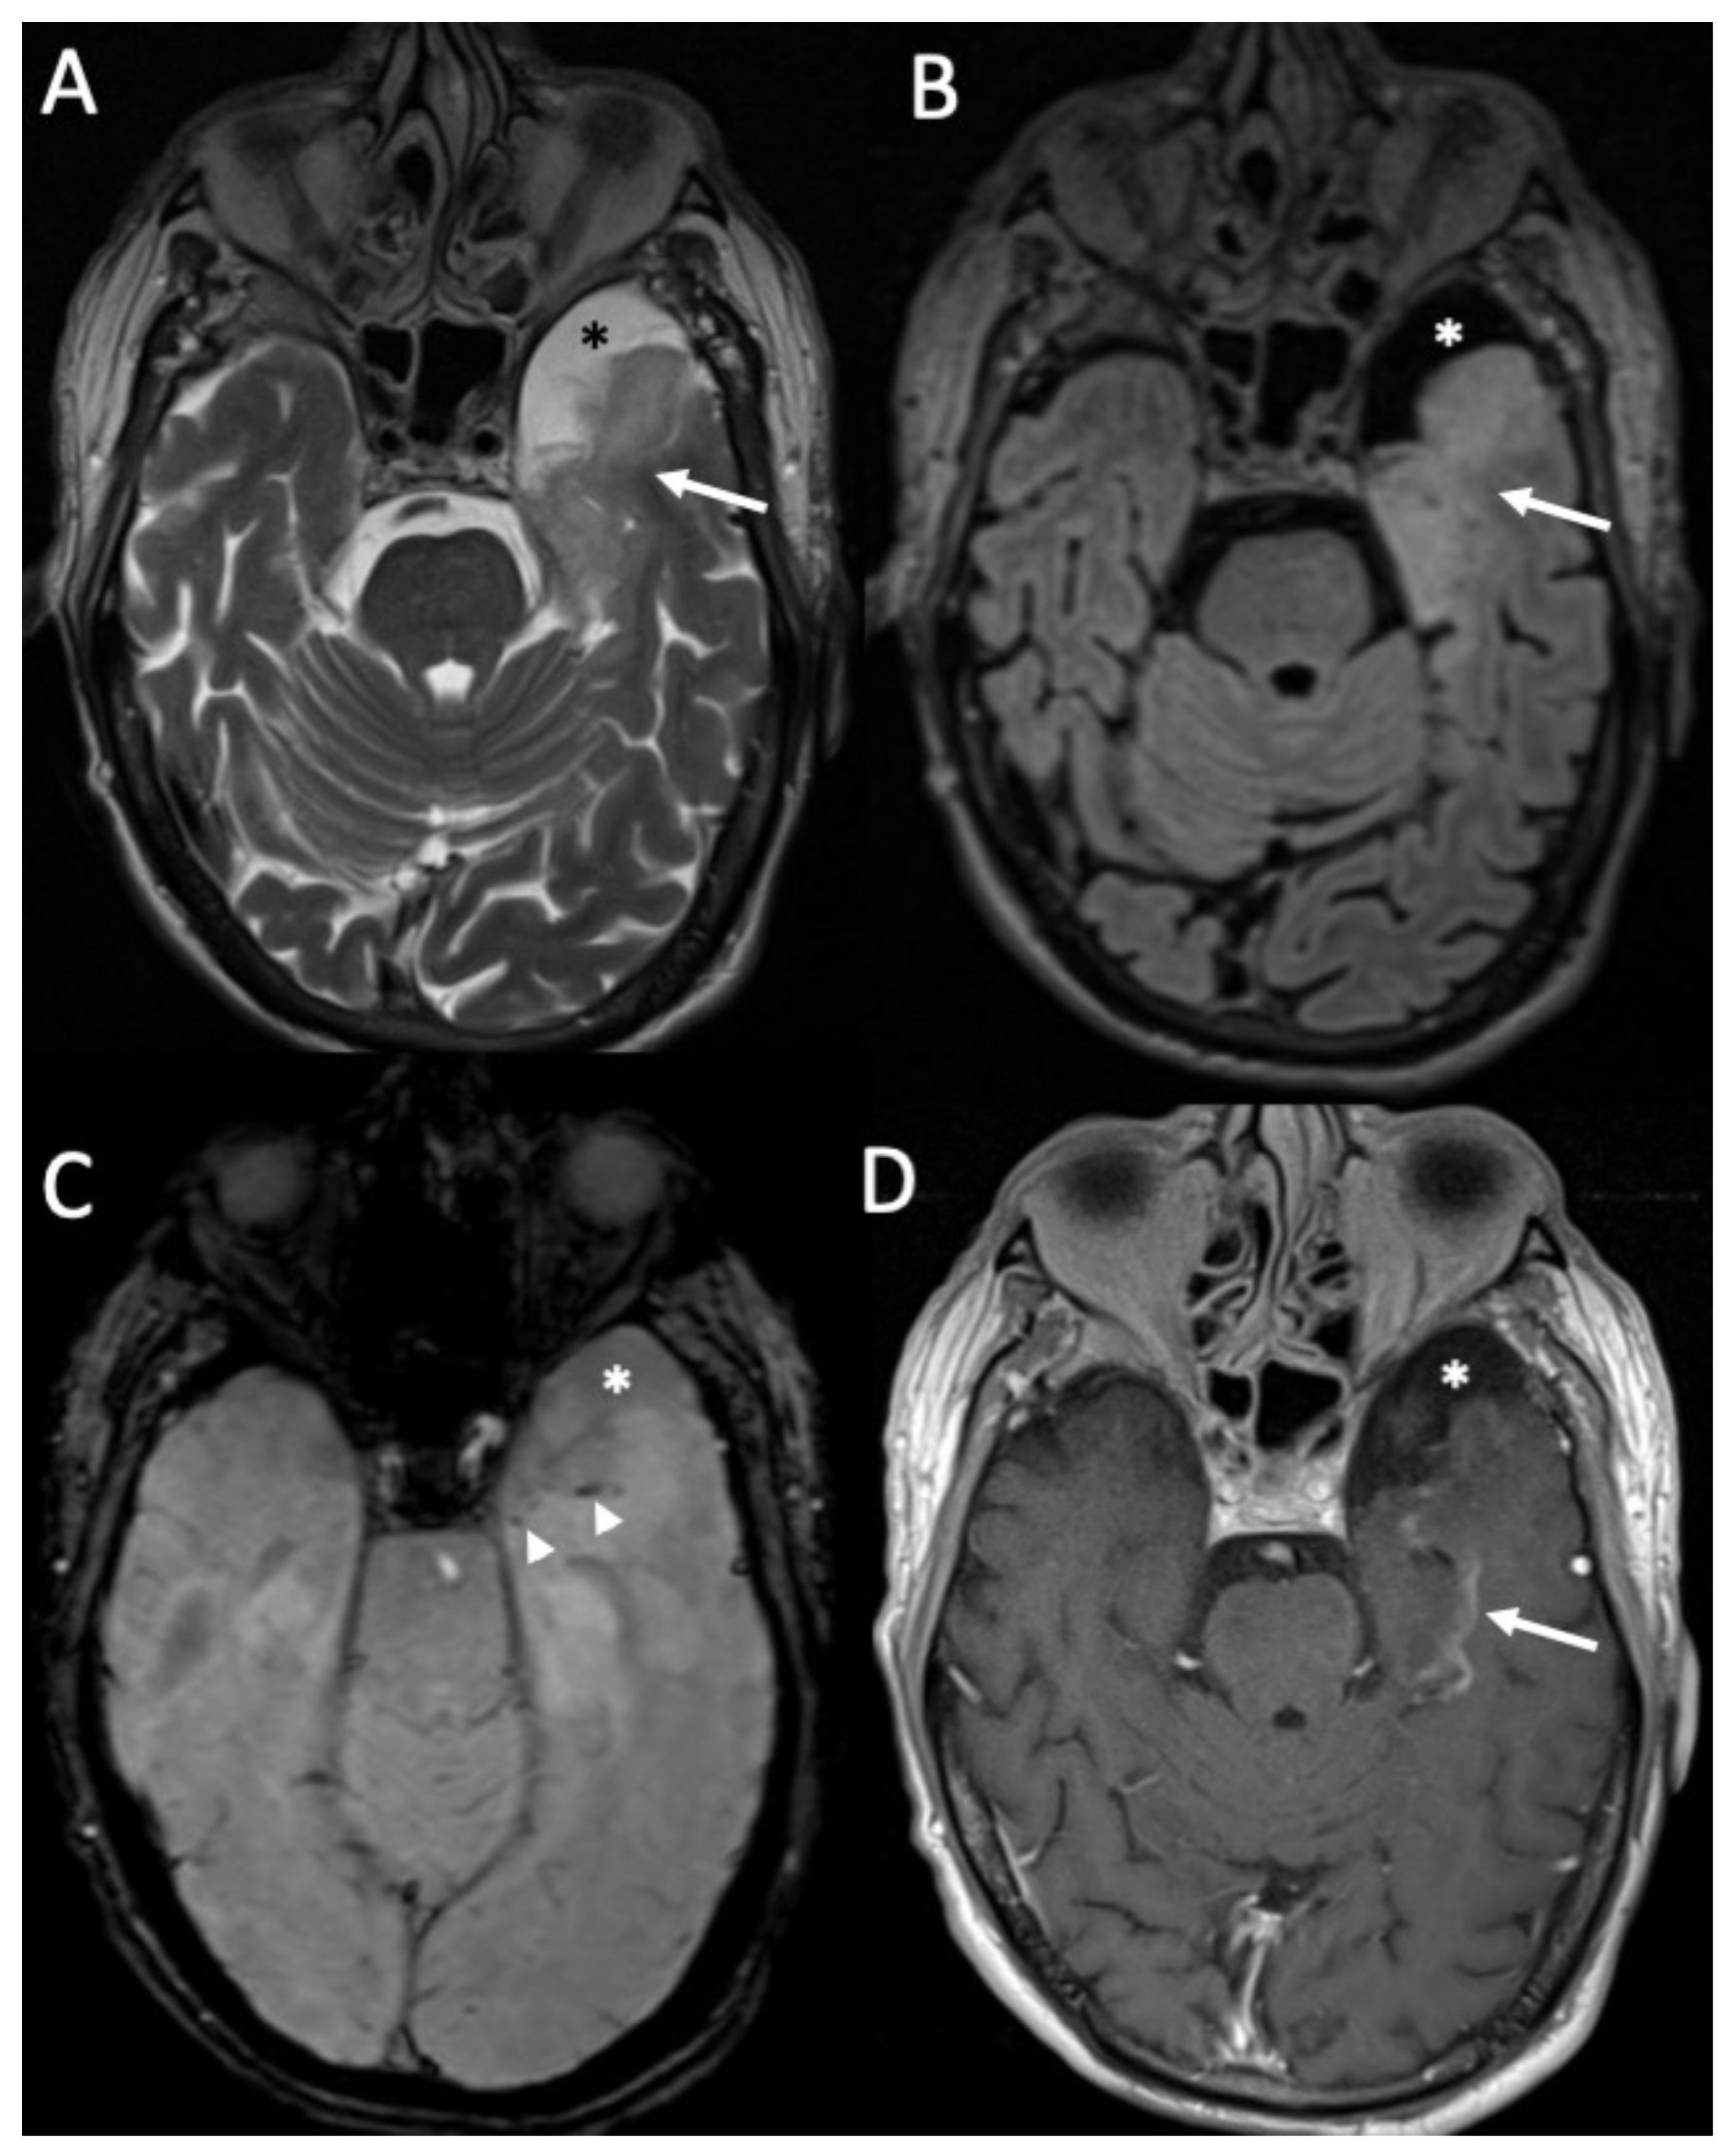

| Herpes Virus type 1 | • Mesio-temporal involvement • Bilateral and asymmetric pattern • Cortical hyperintensity on T2 and FLAIR, with restricted diffusion (acute phase) and cortical enhancement (subacute phase) • Hemorrhagic foci |

5. Viral Meningitis and Encephalitis